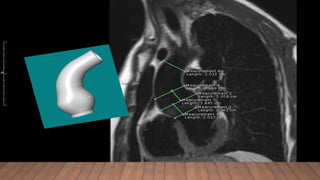

• In the instance of poor echocardiographic windows, magnetic resonance

imaging (MRI) or computed tomography (CT) angiograms should be

performed.

• Routine CT or MRI imaging of the entire thoracic aorta is recommended in

patients who present with descending aortic dilation, type B aortic

dissection, or following ascending aortic aneurysm repair

• Personalized external aortic support (PEARS) is an experimental surgical

alternative being investigated in Europe, which has so far been applied in young

adults only, mostly in the setting of MFS .

• The patient's own aortic dimensions are used to manufacture a replica of the aorta

in plastic on which a bespoke external support is made of a fabric mesh. This can

be positioned around the aortic root and ascending aorta without cardiopulmonary

bypass and involves a shorter operation, than that for the conventional approach